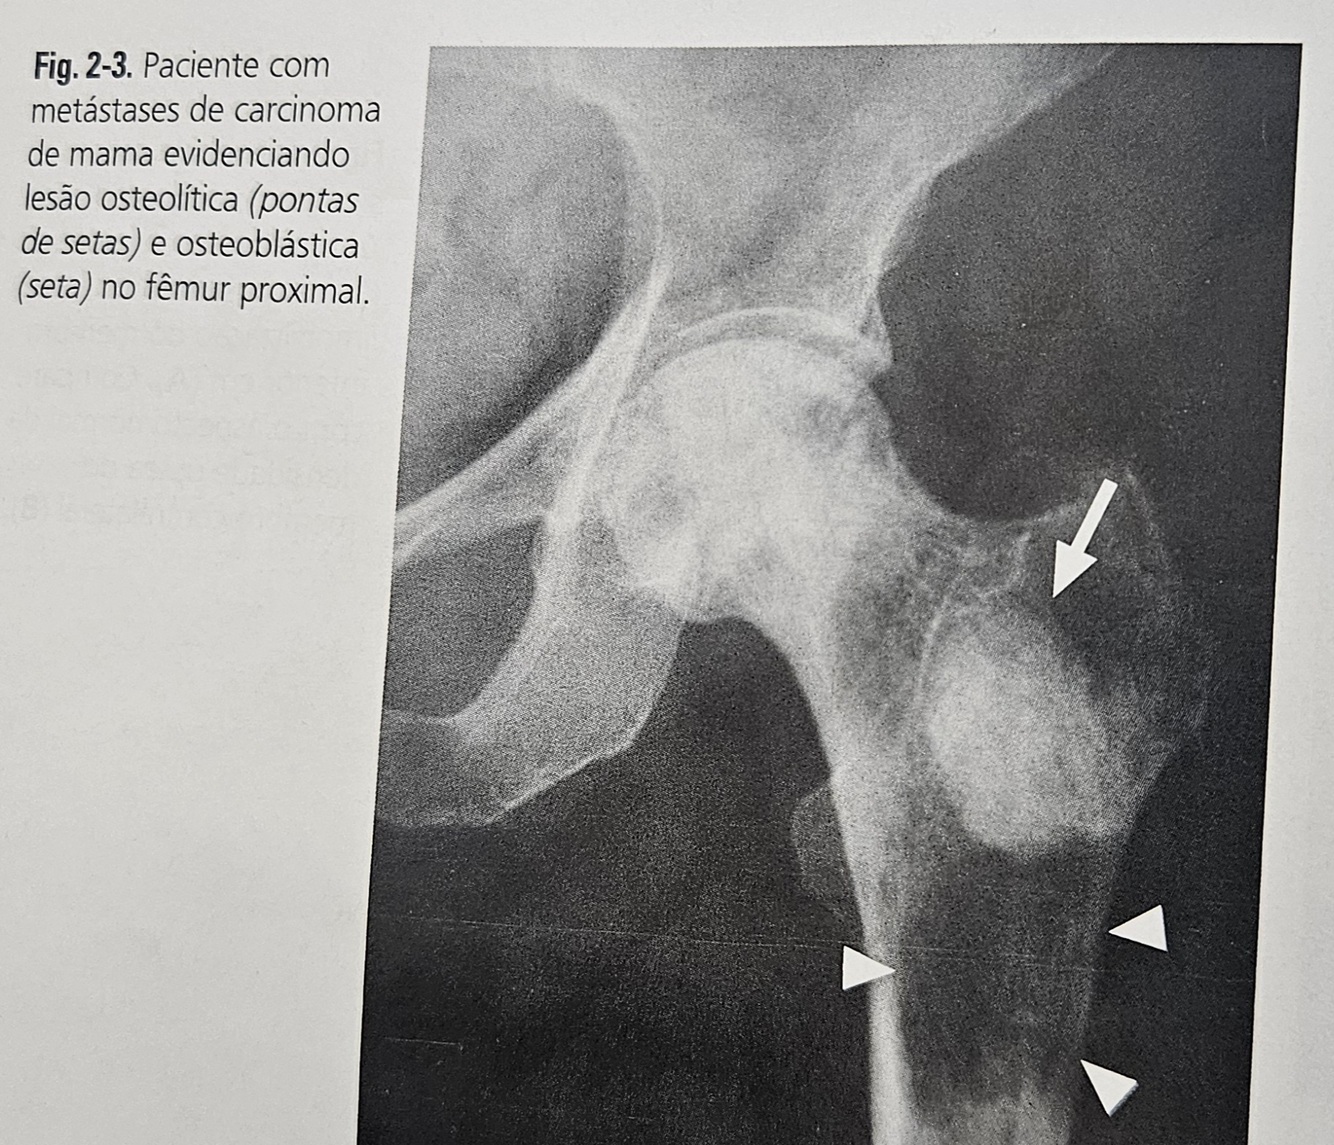

O que você entende por LESÕES OSTEOLITICAS e como elas podem se manifestar?

São as que acarretam destruição óssea e podem se manifestar como uma lesão destrutiva, com reação periosteal ou lesão radiotransparente circunscrita.

O que você entende por LESÕES OSTEOBLASTICAS?

São LESÕES formadoras de tecido anômalo, patológico, apresentando-se com áreas de maior densidade (hiperdensa) radiografica.